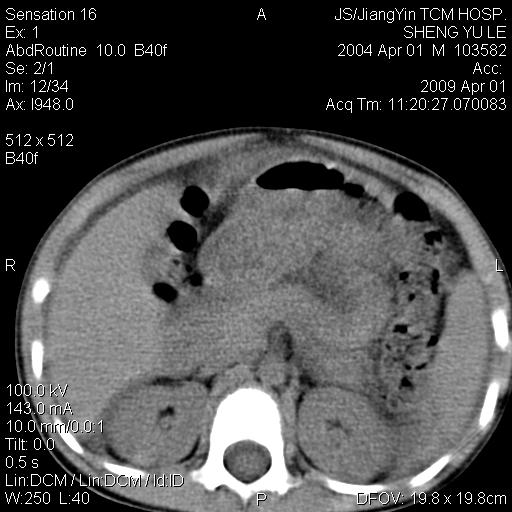

m,5岁。尿痛尿频数天。既往无病史。ct平扫腹盆腔积液。膀胱壁明显增厚。另可见心包增厚。wbc5万,骨髓穿等结果。请指教。

膀胱影像表现结合临床应该是急性膀胱炎症,但为什么有腹水呢?双肾输尿管无扩张,泌尿系压力应该不大不至于引起尿外渗,应该是腹膜感染引起的,但楼主没有提及相关症状,腹膜及膀胱结核?患者白细胞5万(结核不至于这么高啊),脾脏增大,是不是有白血病?进一步检查。。